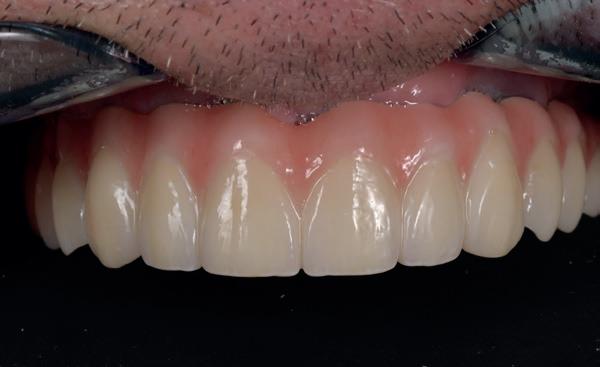

patiënt kon 2 maanden functioneren met de tijdelijke brug, waarna een kort consult werd gepland om te bespreken of hij tevreden was met de esthetiek en functie. Voor de patiënt hoefde niks veranderd te worden (afbeelding 11-14).

14. Portretfoto met tijdelijke brug

20. Frontaanzicht brug

De technicus leverde op basis van de tijdelijke brug, de vast brug op implantaten af. Deze is van volledig zirkoonoxide met een titanium frame aan de binnenzijde voor de stevigheid (afbeelding 16-18). Een volledige brug van alléén zirkoonoxide is namelijk fractuur gevoelig. Na verwijderen van de tijdelijke brug kon de mondhygiëne van de patiënt gecontroleerd worden bij de implantaten. Patiënt hield het netjes schoon met een elektrische tandenborstel en een waterpik. Het is van belang dat de brug zonder spanning op zijn plek geduwd kan worden en deze niet kan kantelen op de abutments. Na het plaatsen van de brug werden de schroefjes getorqued op 15 Ncm, waarna de esthetiek, occlusie en articulatie gecontroleerd konden worden.

Daarna werden de schroefgaten gevuld met Blue M gel, teflon tape en composiet (afbeelding 19 en 20). Patiënt was zich zeer tevreden met het functionele en esthetische eindresultaat (afbeelding 19 en 20). Er was ook een nette hoektand en frontgeleiding. Voor de fonetiek werd een filmpje opgenomen, de F en de S werden netjes uitgesproken (afbeelding 21). De patiënt vervolgt zijn parodontale nazorg bij de mond-